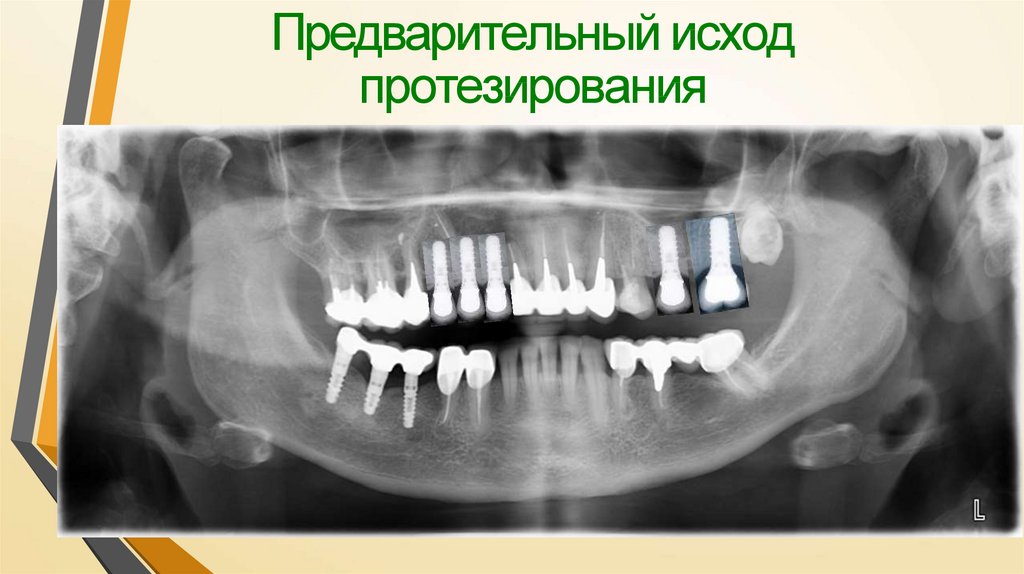

Предварительный исход протезирования

5. Предварительный исход протезирования